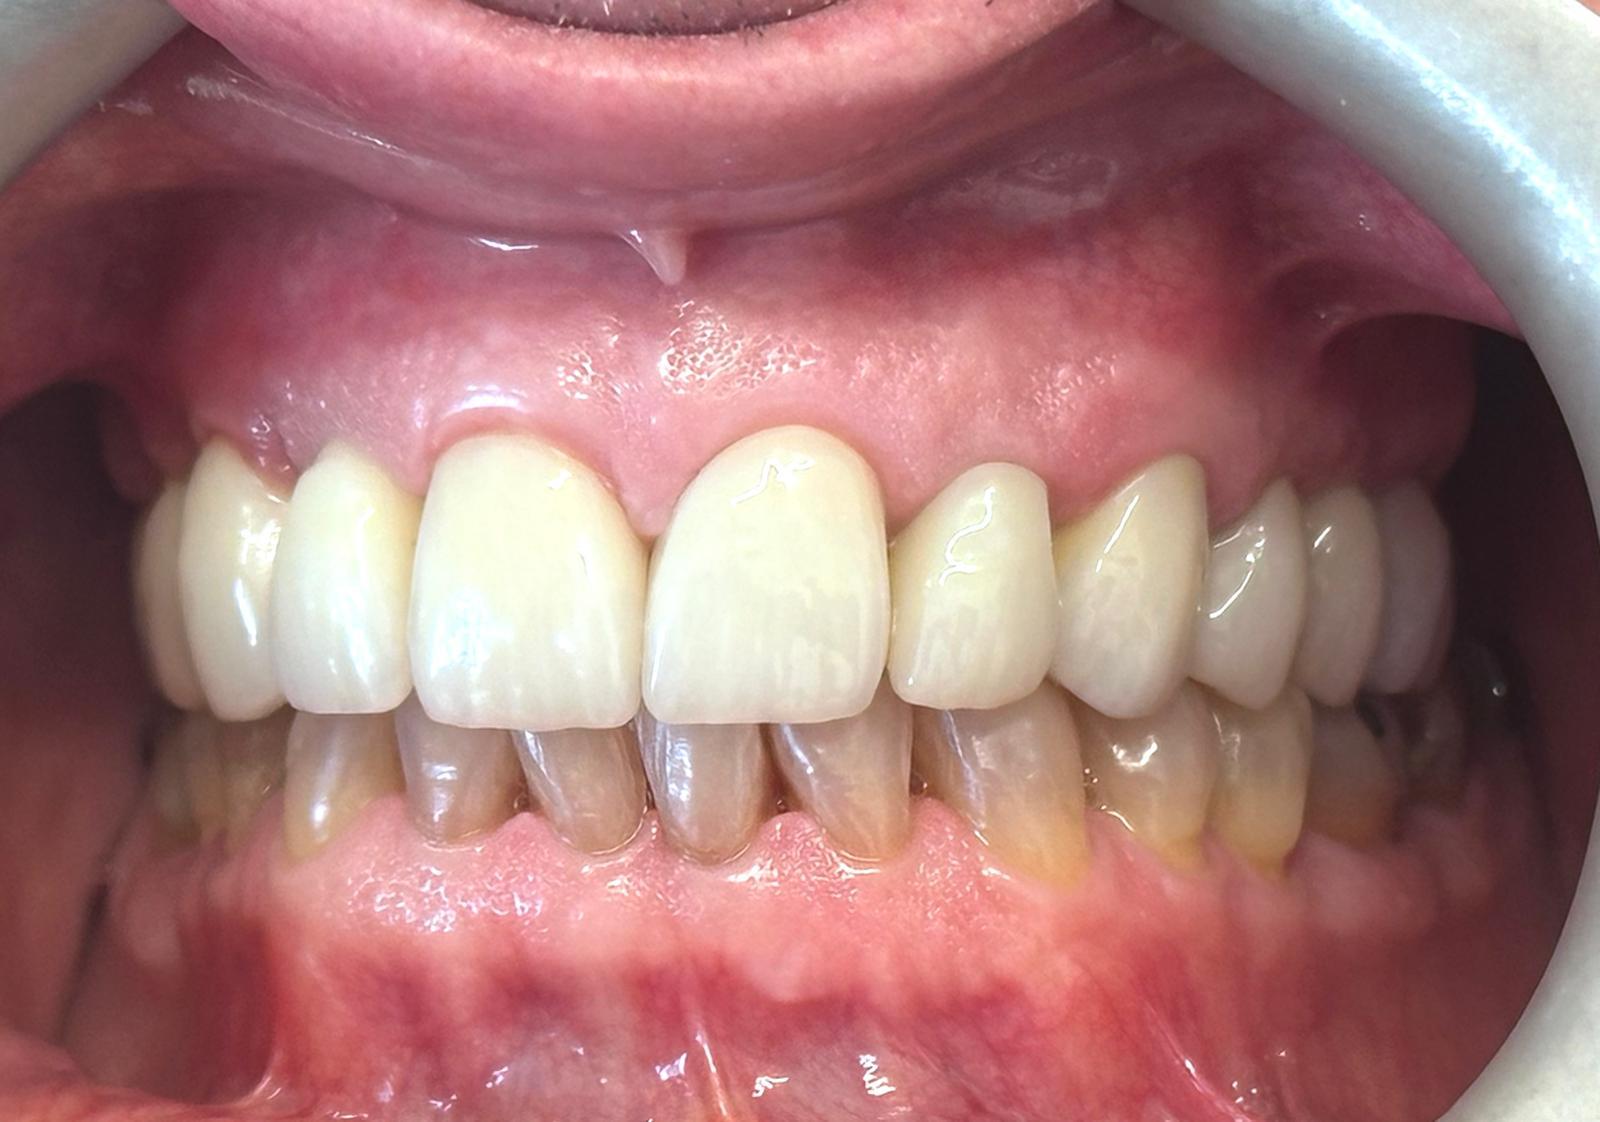

Full smile rehabilitation involving replacement of missing and failing teeth with implant-supported restorations, combined with aesthetic correction of existing dentition. The treatment was carefully planned to restore function, improve alignment, and achieve a balanced, natural-looking smile.

Implants were strategically placed to support long-term stability, with particular attention to soft tissue contours and emergence profiles to ensure seamless integration with the surrounding teeth. The final restoration was designed to enhance both aesthetics and bite function, delivering a confident and harmonious result.

This case demonstrates a comprehensive approach to implant and restorative dentistry, combining surgical precision with advanced prosthetic design to achieve predictable, long-term outcomes.